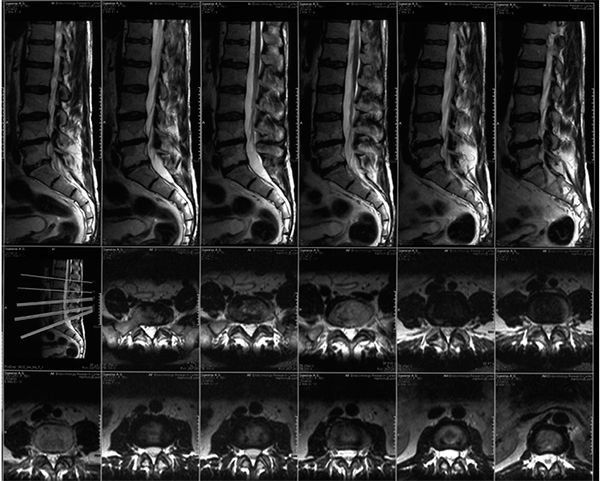

Благодаря исследованию позвоночника методом МРТ врач может изучить анатомическую структуру позвонков, межпозвоночных дисков, спинного мозга и пространств между позвонками, где проходят нервные пучки, тем самым обеспечивая практически полное анатомическое отображение исследуемой области при отсутствии лучевой нагрузки на организм. Изображение получается в 3-х взаимно-перпендикулярных областях, а также, как и при КТ, возможно выполнение трехмерной реконструкции. Исследование с использованием контрастных препаратов повышает диагностическую эффективность метода путем лучшей дифференциации нормальных и отдельных патологических структур.

МРТ позвоночника с контрастом при опухоли позволяет при проникновении препарата внутрь контрастировать места поражения, что показывает патологические структуры, исходно имевшие МР-характеристики, близкие к нормальным окружающим тканям. ТакжеМРТ снимок позвоночника часто бывают ситуации, когда опухоль сливается с отеком, который может ее окружать или мешает интерпретации сигнал от спинномозговой жидкости. Введение контрастного препарата, чаще всего парамагнетика, позволяет получить интенсивный однородный сигнал от опухоли, четко отграниченного от окружающего отека, что позволяет точно судить об истинных размерах опухолевого поражения. Также улучшается визуализация внутри- и внеопухолевых кист, областей некроза. Все это способствует определению точной тактики лечения и помогает в выборе объема оперативного вмешательства.